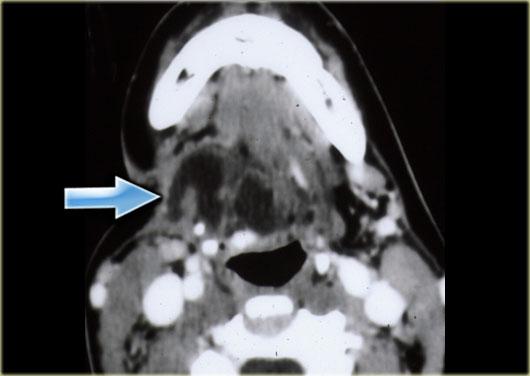

Paraganglioma: Hình ảnh MRI chuỗi xung T1W có tiêm thuốc tương phản từ Gadolinium tại mức thanh quản trên thanh môn

Paraganglioma

Bước 1: Xác định khoang

Bên trái là hình ảnh một bệnh nhân có khối sưng ở bên trái cổ.

Hãy quan sát hình ảnh MRI tại mức thanh quản trên thanh môn và xác định tổn thương nằm trong khoang nào.

Sau đó tiếp tục đọc.

Khối sưng nằm tập trung giữa động mạch cảnh ngoài và động mạch cảnh trong.

Lưu ý rằng các mạch máu này bị chèn ép.

Rõ ràng tổn thương này phải nằm trong khoang cảnh.

Cần lưu ý rằng có một tổn thương nhỏ hơn nhưng có hình thái tương tự, nằm ở khoang cảnh bên phải.

Paraganglioma thường gặp dạng đa ổ ở 3% đến 5% bệnh nhân nói chung và 20% đến 30% ở những người có tiền sử gia đình dương tính.

Các tổn thương này ngấm thuốc mạnh trên CT và MRI như được thấy trên hình ảnh MRI mặt phẳng coronal sau tiêm Gadolinium này.

Trong tổn thương lớn hơn ở bên trái, có thể thấy các vùng mất tín hiệu dòng chảy điển hình (xem thêm hình ảnh mặt cắt ngang).

Vì vậy, chúng ta có thể kết luận rằng có các tổn thương ngấm thuốc mạnh hai bên với hiện tượng mất tín hiệu dòng chảy trong khoang cảnh, nhiều khả năng nhất là u thể cảnh hoặc paraganglioma.